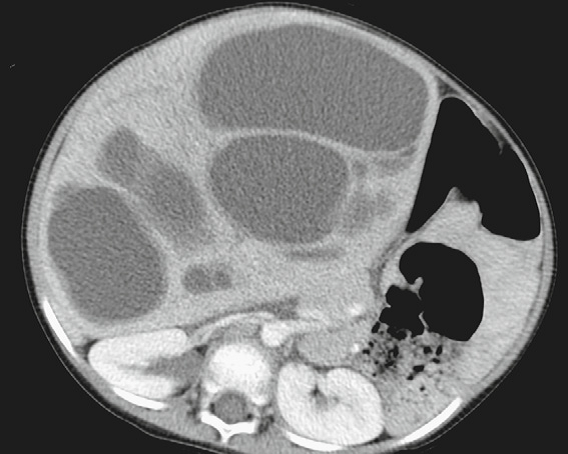

Mesenchymal Hamartoma of the Liver

Large, multilocular, cystic masses with thin internal septations